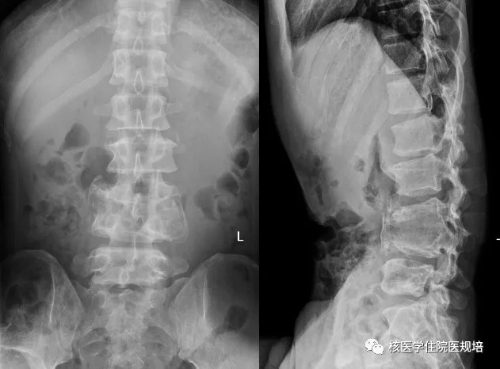

患者男性,30岁, 3个月前无明显诱因突发大小便失禁,同时伴下肢活动障碍,为进一步诊治就诊于我院。既往史:出生后诊断为先天性无痛无汗症,其他无特殊病史。查体:患者轮椅进入病房,神志清楚,对答切题;全身皮肤干燥、见多处瘢痕,皮肤痛觉缺失,指甲发育不良,脊柱生理屈度存在,无明显棘突压痛。双上肢未见明显畸形,肌力、肌张力未见明显异常。左下肢可见膝关节不规则隆起,表面不光滑,质硬,无波动感,关节屈伸正常,局部皮温正常,无皮肤红肿、破溃或静脉怒张,压痛(-);右下肢未见明显异常。双下肢感觉较弱,巴氏征(-)。实验室检查无明显异常发现。腰椎X光片及CT(图1.2)检查发现腰椎退行性变,L3、L4椎体融合,骨小梁结构模糊,L5/S1椎间盘膨出,前纵韧带钙化;多关节部位X光片示右髋关节(图3)髋臼扩大、骨质吸收,股骨头脱位,骨骺未融合,残端如刀削状,关节肿胀,内见多发碎骨片;左膝关节(图4)正常关节结构消失,关节对位差,骨端膨大,周围见多发游离骨块,股骨下段、胫骨平台见骨质破坏,关节周围软组织肿胀;右踝关节(图5)诸骨在位,胫腓骨远端膨大变形,距骨变扁,诸骨骨质密度弥漫减低,骨小梁稀疏,内外踝边缘可见骨质增生;关节间隙狭窄。为进一步了解全身骨病变情况行99mTc-MDP全身骨显像(图6)。

图2.